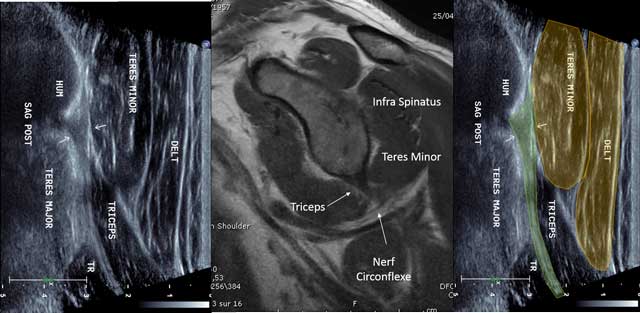

Figure 9

Sagittal view of the triceps tendon with MRI correlation. HUM: Humerus, TR: Triceps muscle, Nerf circonflexe: circumflex nerve.